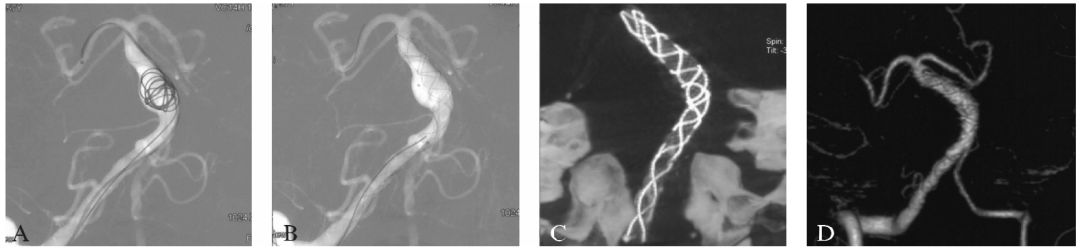

7F导引导管超选至右侧椎动脉的C₁~C₂水平。使用双导管技术,由于基底动脉扩张段的管径明显大于支架管径,因此我们使用1枚Cosmos 10mm/36cm的弹簧圈在基底动脉扩张处释放但不解脱,从而辅助稳定另1根微导管释放支架(图16-2A)。使用多支架的Telescoping技术,植入2枚LEO支架重建动脉管腔(图16-2B),并在支架释放后撤出弹簧圈,Dyna CT示支架之间部分重叠覆盖(图16-2C)。术后患者症状减轻,第7天时症状完全消失。

图16-2患者首次介入治疗的过程及术后复查影像

A:在基底动脉膨胀部位暂时植入弹簧圈为支架作支撑;

B:使用Telescoping技术释放2枚LEO支架覆盖病变动脉,而后收回弹簧圈以减少局部血流动力学影响;

C:术后Dyna CT显示支架的形态(前后位观);

D:术后1个月CTA复查示病变瘤样扩张消失,管径与支架管径一致